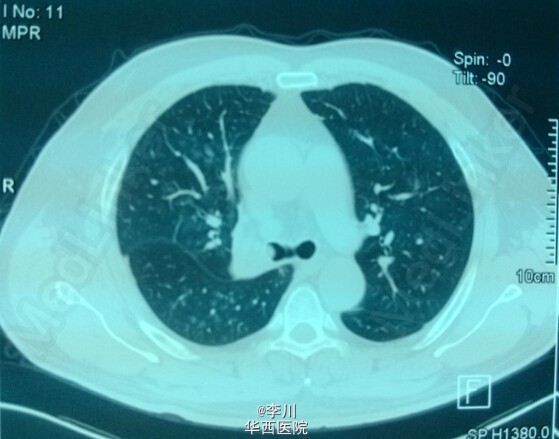

大医院技术更好?---右上肺鳞癌伴肺不张一例

患者为50岁男性,因咳嗽咳痰、痰中带血3+月入院。3+月前患者因上述症状于当地医院就诊,行相关检查后诊断为右肺上叶鳞癌。却被告知不能手术,只能放化疗。患者不甘心,遂于我院就诊,经我院知名专家详细读片评估后,认为有手术指证,首选手术治疗。查体心腹无特殊异常。右上肺呼吸音弱,未闻及干湿罗音,左肺呼吸音无明显异常。